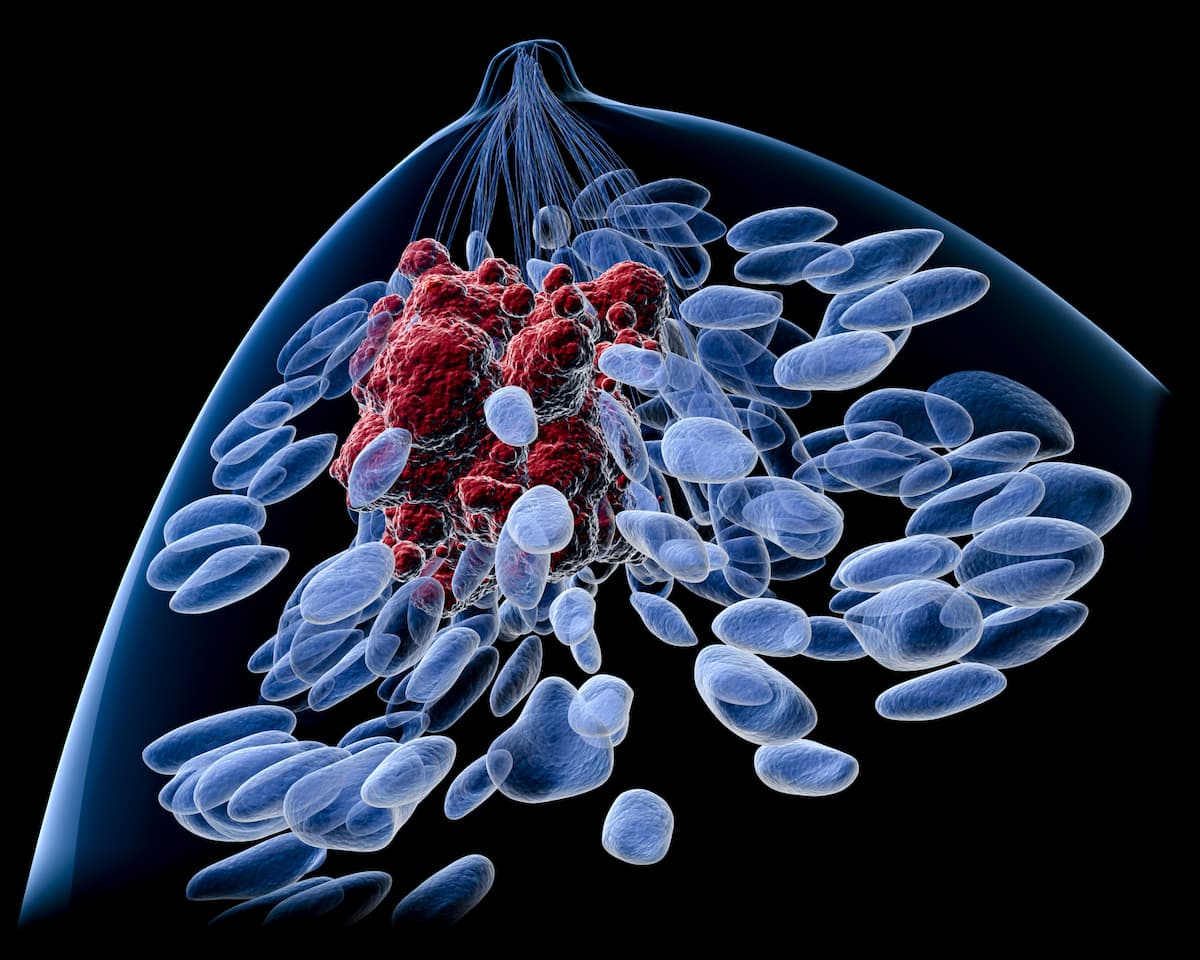

Chemo Effects May Outweigh Obesity-Related GI Alterations in Breast Cancer

The effects of obesity-related gastrointestinal (GI) microbiome alterations and their impact on symptom burden may be outweighed by the effects of chemotherapy in patients with breast cancer, according to findings from a poster presentation at the 50th …